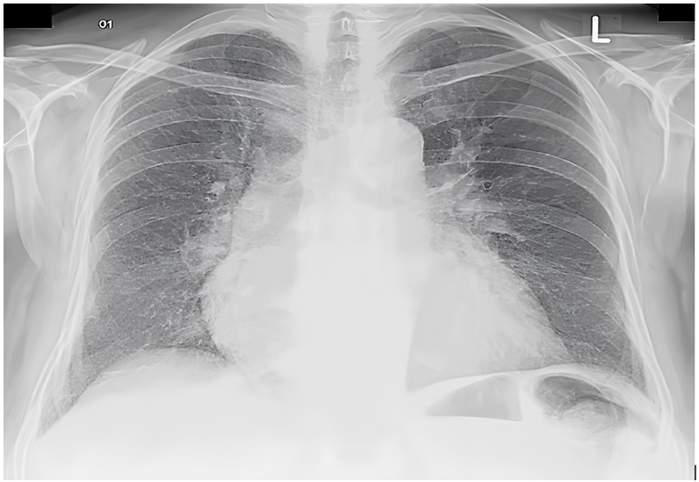

Homem, 65 anos, hipertenso e diabético, vai à emergência por dispneia súbita e dor torácica intensa. Seus sinais vitais são: PA 170/110 mmHg, FC 92 bpm, FR 26 mpm, spO2 92% em ar ambiente. Ao eletrocardiograma e à radiografia de tórax, tem-se os seguintes achados:

Enunciado 4713563-1

Enunciado 4713563-2

Inicialmente, o paciente é colocado em máscara de Hudson a 10 L/min com infusão de nitroglicerina endovenosa, apresentando melhora dos sintomas. Na sequência, o paciente apresenta PA 76/40 mmHg e FC de 120 bpm. Além de suspender a nitroglicerina, qual é a próxima conduta mais adequada para esse paciente?